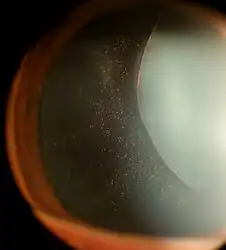

Ectopia Lentis in Marfan syndrome. Zonular fibers are being seen. | |

Ectopia lentis is a displacement or malposition of the eye's crystalline lens from its normal location. A partial dislocation of a lens is termed lens subluxation or subluxated lens; a complete dislocation of a lens is termed lens luxation or luxated lens.